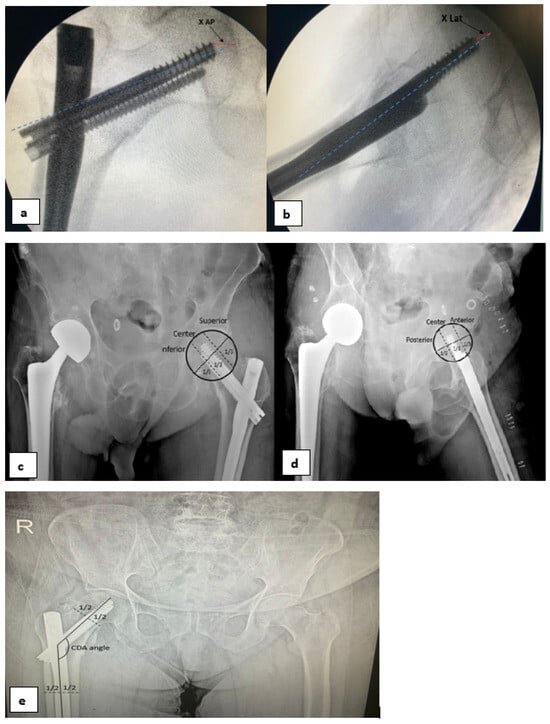

Preoperative data on the patient’s age, gender, and preoperative comorbidities (diabetes, hypertension, coronary artery disease, heart failure, renal failure, asthma, COPD—chronic obstructive pulmonary disease, dementia, and cerebrovascular disease) were collected. Additionally, the American Society of Anesthesiologists Physical Status Classification System (ASA) score and the number of days between the occurrence of the fracture and surgery were examined. Perioperative data included the duration of surgery from the beginning of anesthesia until the patient left the operating room. For the postoperative period, postoperative complications, length of stay in the hospital, and length of stay in the intensive care unit were examined, while in postoperative radiographs, tip–apex distances (TADs), collodiaphyseal angles (CDAs) (Figure 2), and Cleveland–Bosworth quadrants were examined to evaluate the placement of the lag screw in the femoral head (Figure 3). Two orthopedists performed radiological measurements and categorization using anteroposterior and lateral pelvic radiographs. In addition, screw cut-out evaluations were made during the follow-ups. The quality of fracture reduction was evaluated according to the modified Baumgaertner criteria (Table 1). The adequacy of reduction was classified as good, acceptable, or poor [9].

Figure 2. Methods of measuring TAD values. TAD = [Xap × (Dtrue/Dap)] + (Xlat × (D true/Dlat)] (Dtrue = known diameter of the lag screw) (a,b). Determination of quadrant in the anteroposterior view and lateral view (c,d). Measurement of the collodiaphyseal angle (CDA) (e).